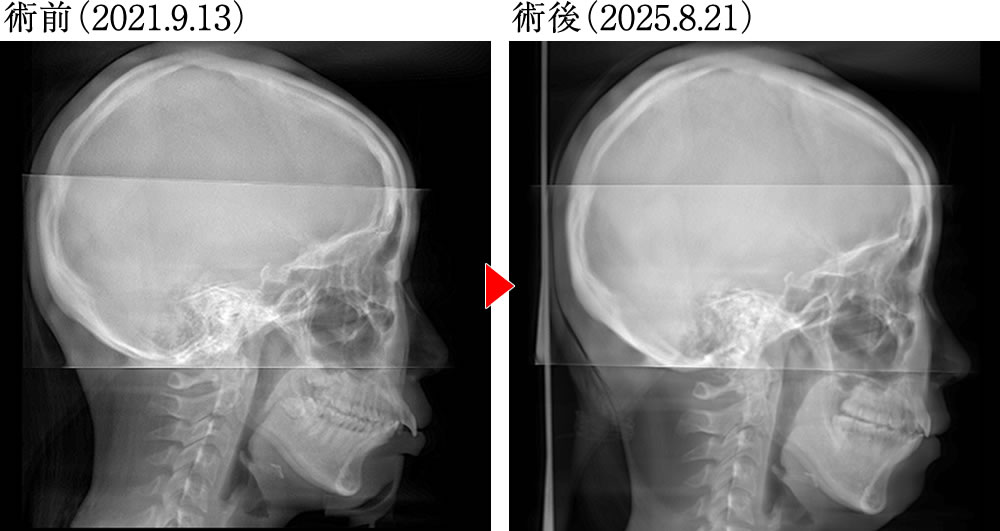

術前術後の骨格の変化

術前は、親知らずが残存しており、上顎前歯の位置や傾斜に問題があることで下顎が後退した噛み合わせでした。術後は咬合平面がフラットに整い、前歯の傾斜が大きく改善され、下顎が前方に誘導された位置で噛めるようになり、正しい被蓋関係の歯並びとなりました。